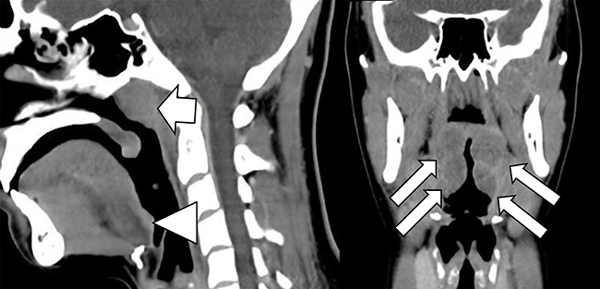

Preparado anatómico. Cortes sagital y coronal mostrando las estructuras del anillo de Waldeyer. Se demarcan las principales estructuras que conforman el anillo de Waldeyer: amígdalas palatinas (flechas largas), amígdalas faríngeas o adenoides (flecha corta) y amígdalas linguales (cabeza de flecha).

Cortes sagital y coronal de TC de la faringe. Paciente de 16 años asintomática. Se demarca la hipertrofia fisiológica de las principales estructuras que conforman el anillo de Waldeyer: amígdalas palatinas (flechas largas), amígdalas faríngeas o adenoides (flecha corta) y amígdalas linguales (cabeza de flecha).